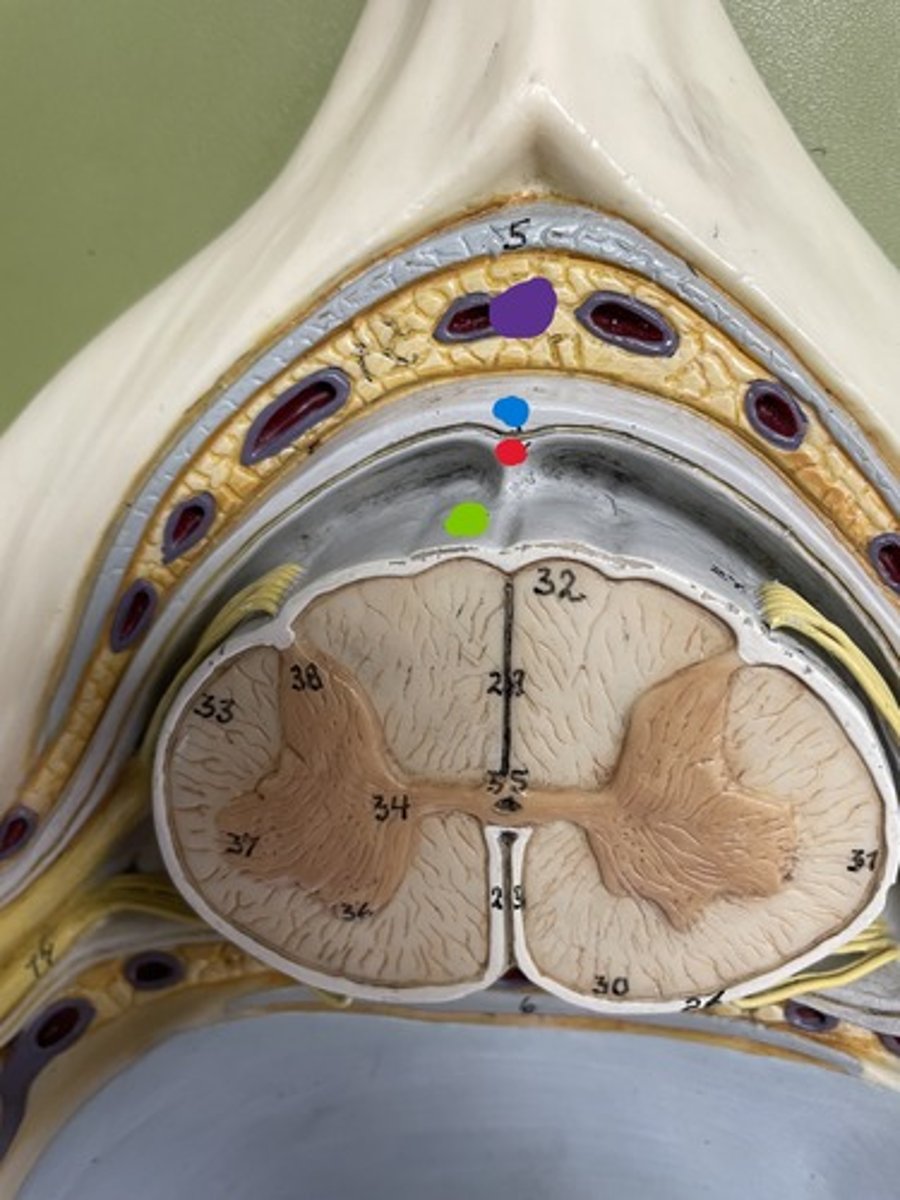

Cervical enlargement

Blue

Lumbar enlargement

Purple

Conus medullaris

Green

Gray matter

Posterior horn

Anterior horn

Lateral horn

G

Gray commissure

gray matter around this structure

Central canal

White matter

Posterior funiculus

Green

Anterior funiculus

Yellow

Lateral funiculus

Red

Posterior median sulcus

green

Anterior median fissure

red

Dura mater

blue

Arachnoid mater

red

Pia mater

green

Epidural space

purple

Subdural space

between red and blue

Subarachnoid space

between red and green